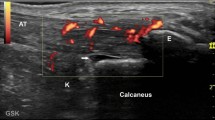

IVIS analysis

The changes in the signal intensities pre-injection and 120 min after injection were assessed. Representative images of 14 weeks of age control mice and MR16–1 treated mice are shown in Fig. 6a and b. MR16–1 treated mice did not show ICG accumulation in the ankle or foot joints. However, control mice showed obvious accumulation in the foot and ankle joints. The results of IVIS analyses are shown in Fig. 7. Quantitative IVIS was carried out at weeks 10, 14 and 18 in control and MR16–1 treated mice. There was a significant difference in the signal intensities of control and MR16–1 treated mice at week 14 (p = 0.041), although there no significant differences were seen at weeks 10 or 18.

Quantitative analyses of signal intensity of IVIS at week 10, 14, 18. At week 14, the signal intensity of IVIS of ankles and foots is significantly lower in MR16–1 treatment group, compared with the control group. There are no significant changes in week 10 and 18 in both groups. Results are expressed as the mean ± standard error (n = 5 mice per group). Representative data are shown from three independent experiments with similar results. * p < 0.05 by two-way ANOVA with Dunn’s multiple comparison test

The results of IVIS analyses showed that there was a significant difference between the two groups in week 14 only. These results are inconsistent with the results of histological analyses, PCR and ELISA of SAA, which indicated significant differences after week 14. We consider that the proliferation of dysfunctional blood vessels in inflamed joints of McH/lpr-RA1 mice decreases around week 18. The histological findings showed significant differences and advanced deformity in late phase arthritis, including bone erosion, pannus formation and ankylosis. The advancement of destructive arthritis and ankylosis after the decreased formation of dysfunctional blood vessels may induce the inconsistent results of IVIS and histological synovitis score.